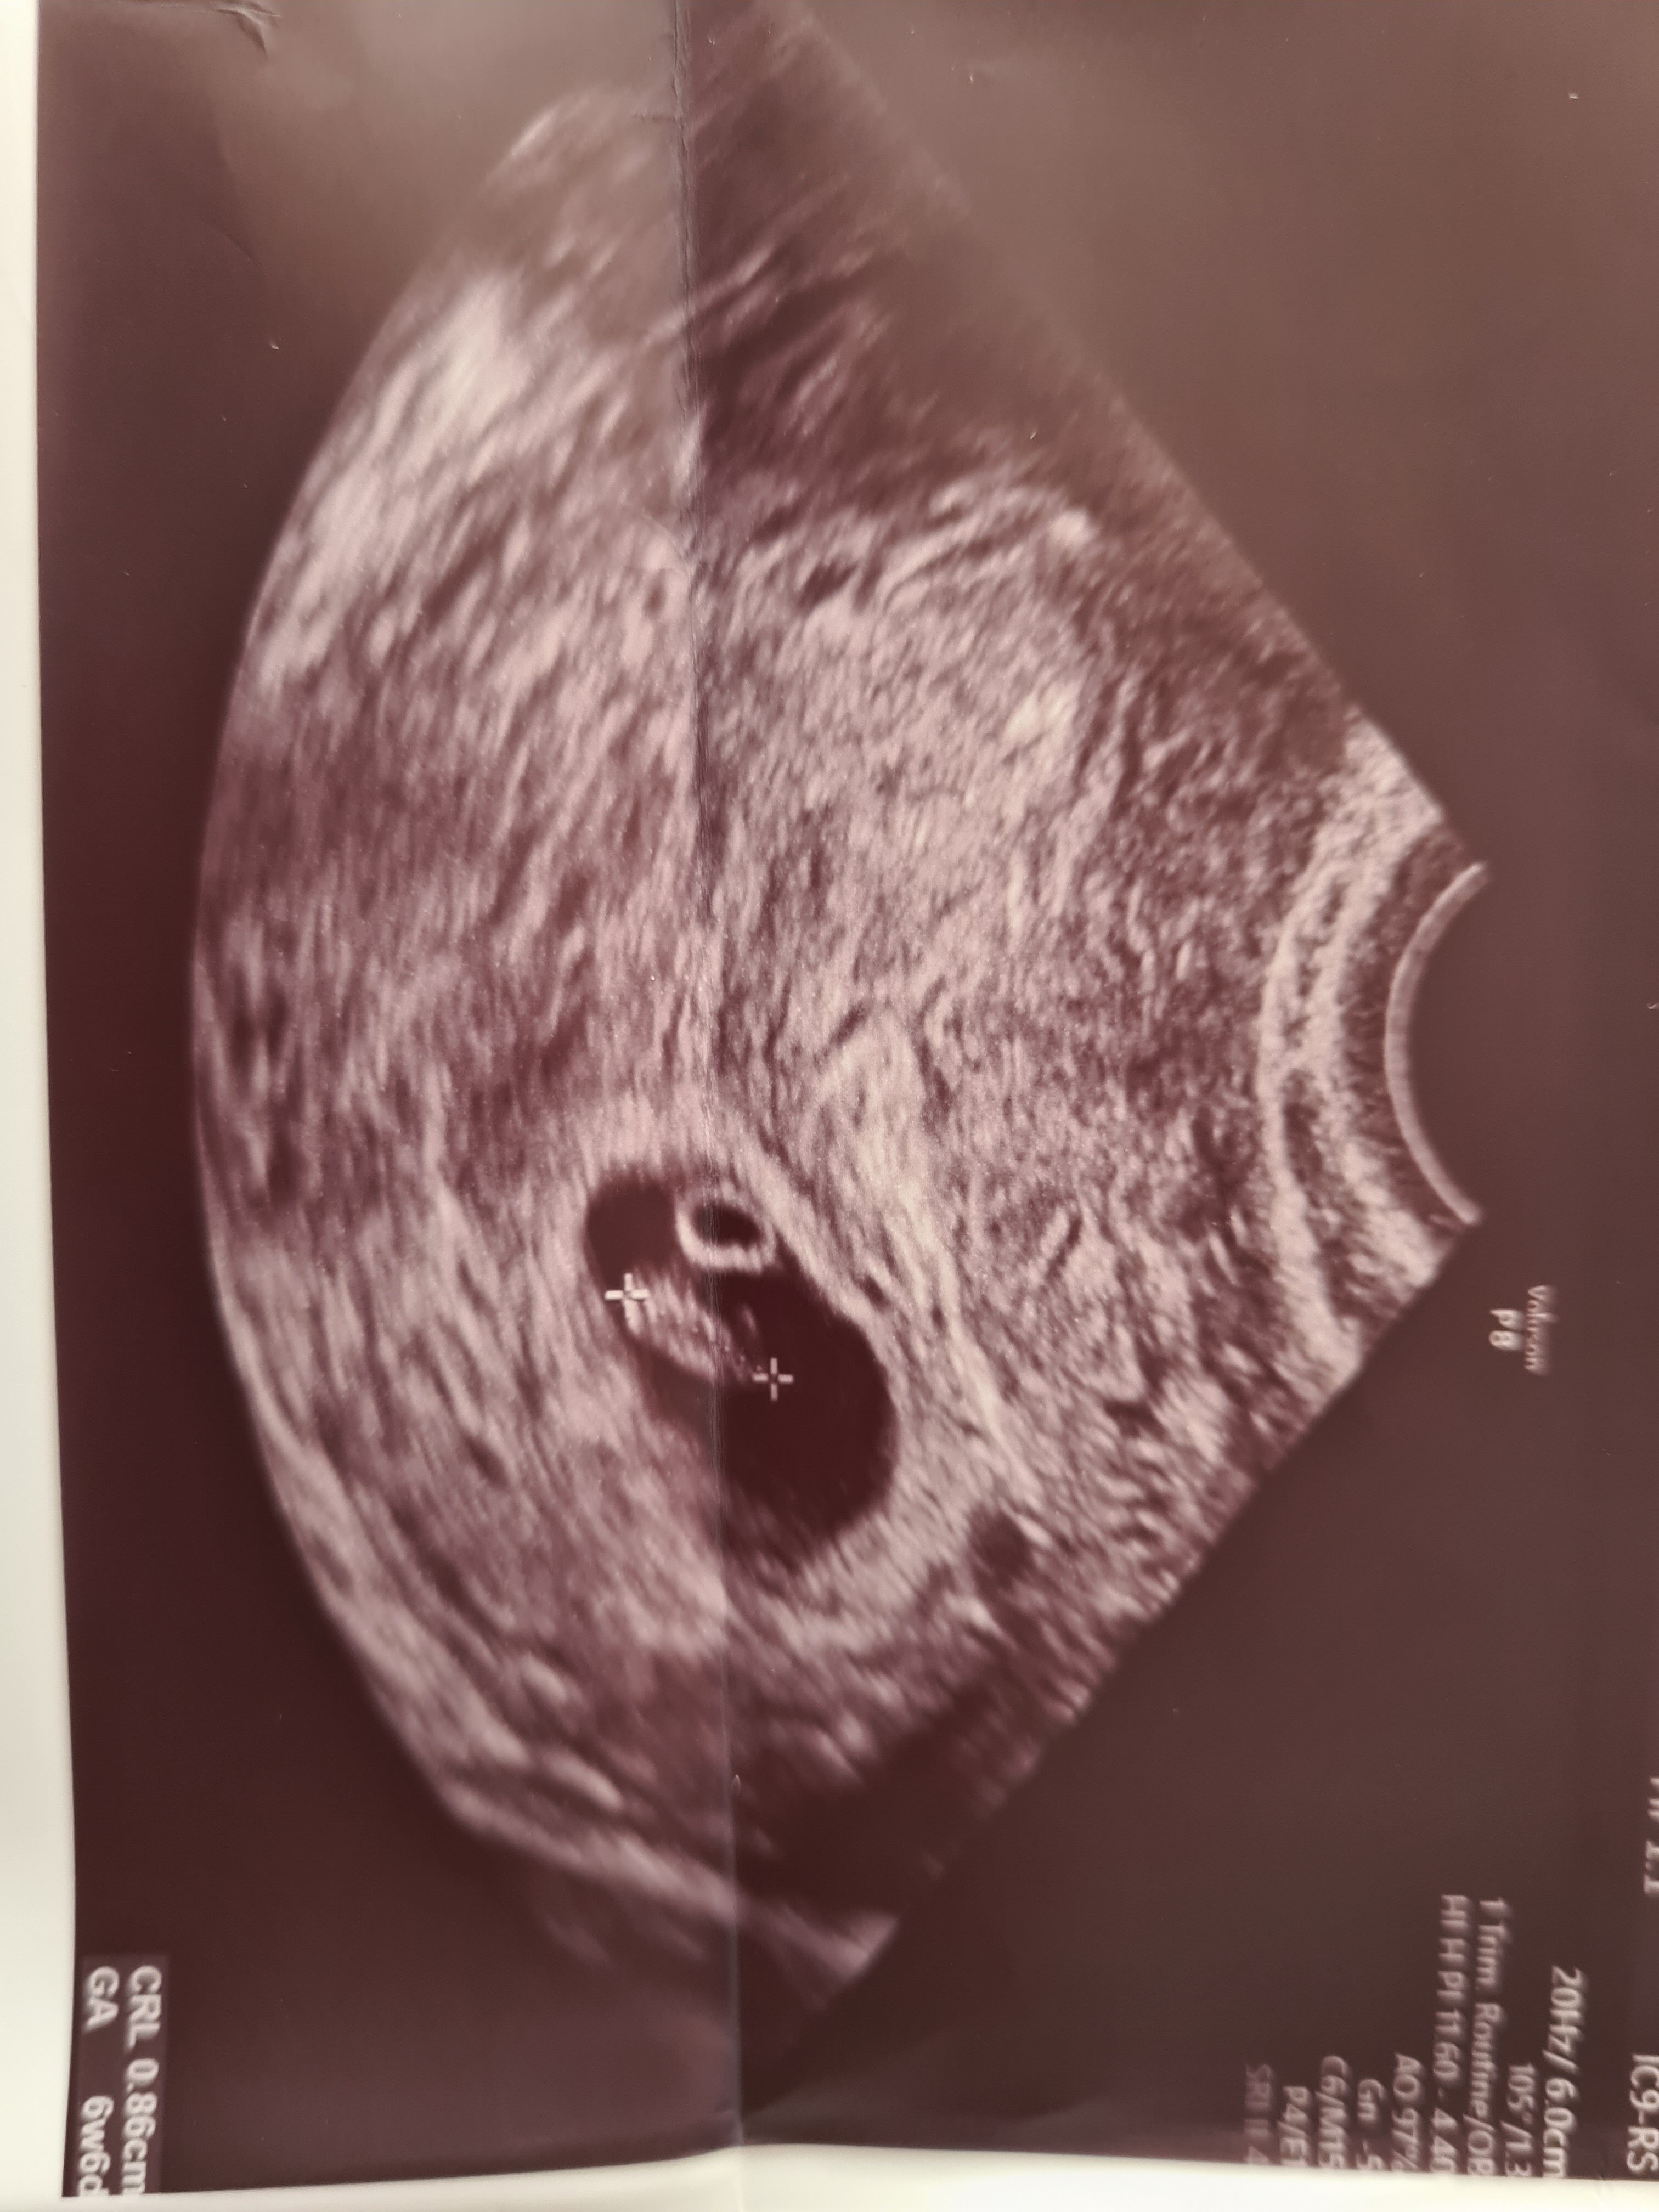

Cześć dziewczyny. Pisałam we wcześniejszych postach o moim krwiaku i plamieniach. To mnie okropnie przerażało. Wczoraj byłam na kontroli u innego lekarza. Dostałam zwiększoną dawkę duphastonu i dodatkowo luteine 200. Dziś już widać diametralną różnicę. Plamienie ustępuje 🤭 Moje maleństwo ma 7.5 mm a serduszko bije 155/min. Lekarz nie założył książeczki ciąży, nie wiem o co chodzi 🤔 przecież już bije serduszko. Wg USG 7 tc

Załączniki

• 20220906_134759.jpg

20220906_134759.jpg

1 MB · Wyświetleń: 84